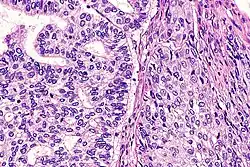

| Micrograph of a lung primary small cell carcinoma, a type of carcinoma. The clustered cancerous cells consist primarily of nucleus (purple); they have only a scant rim of cytoplasm. The surrounding pale staining, discoid cells are red blood cells. Cytopathology specimen. Field stain. | |

- Small cell carcinoma

- Cells are usually round and are less than approximately three times the diameter of a resting lymphocyte and with little evident cytoplasm. Occasionally, small cell malignancies may themselves have significant components of slightly polygonal and/or spindle-shaped cells.[8]